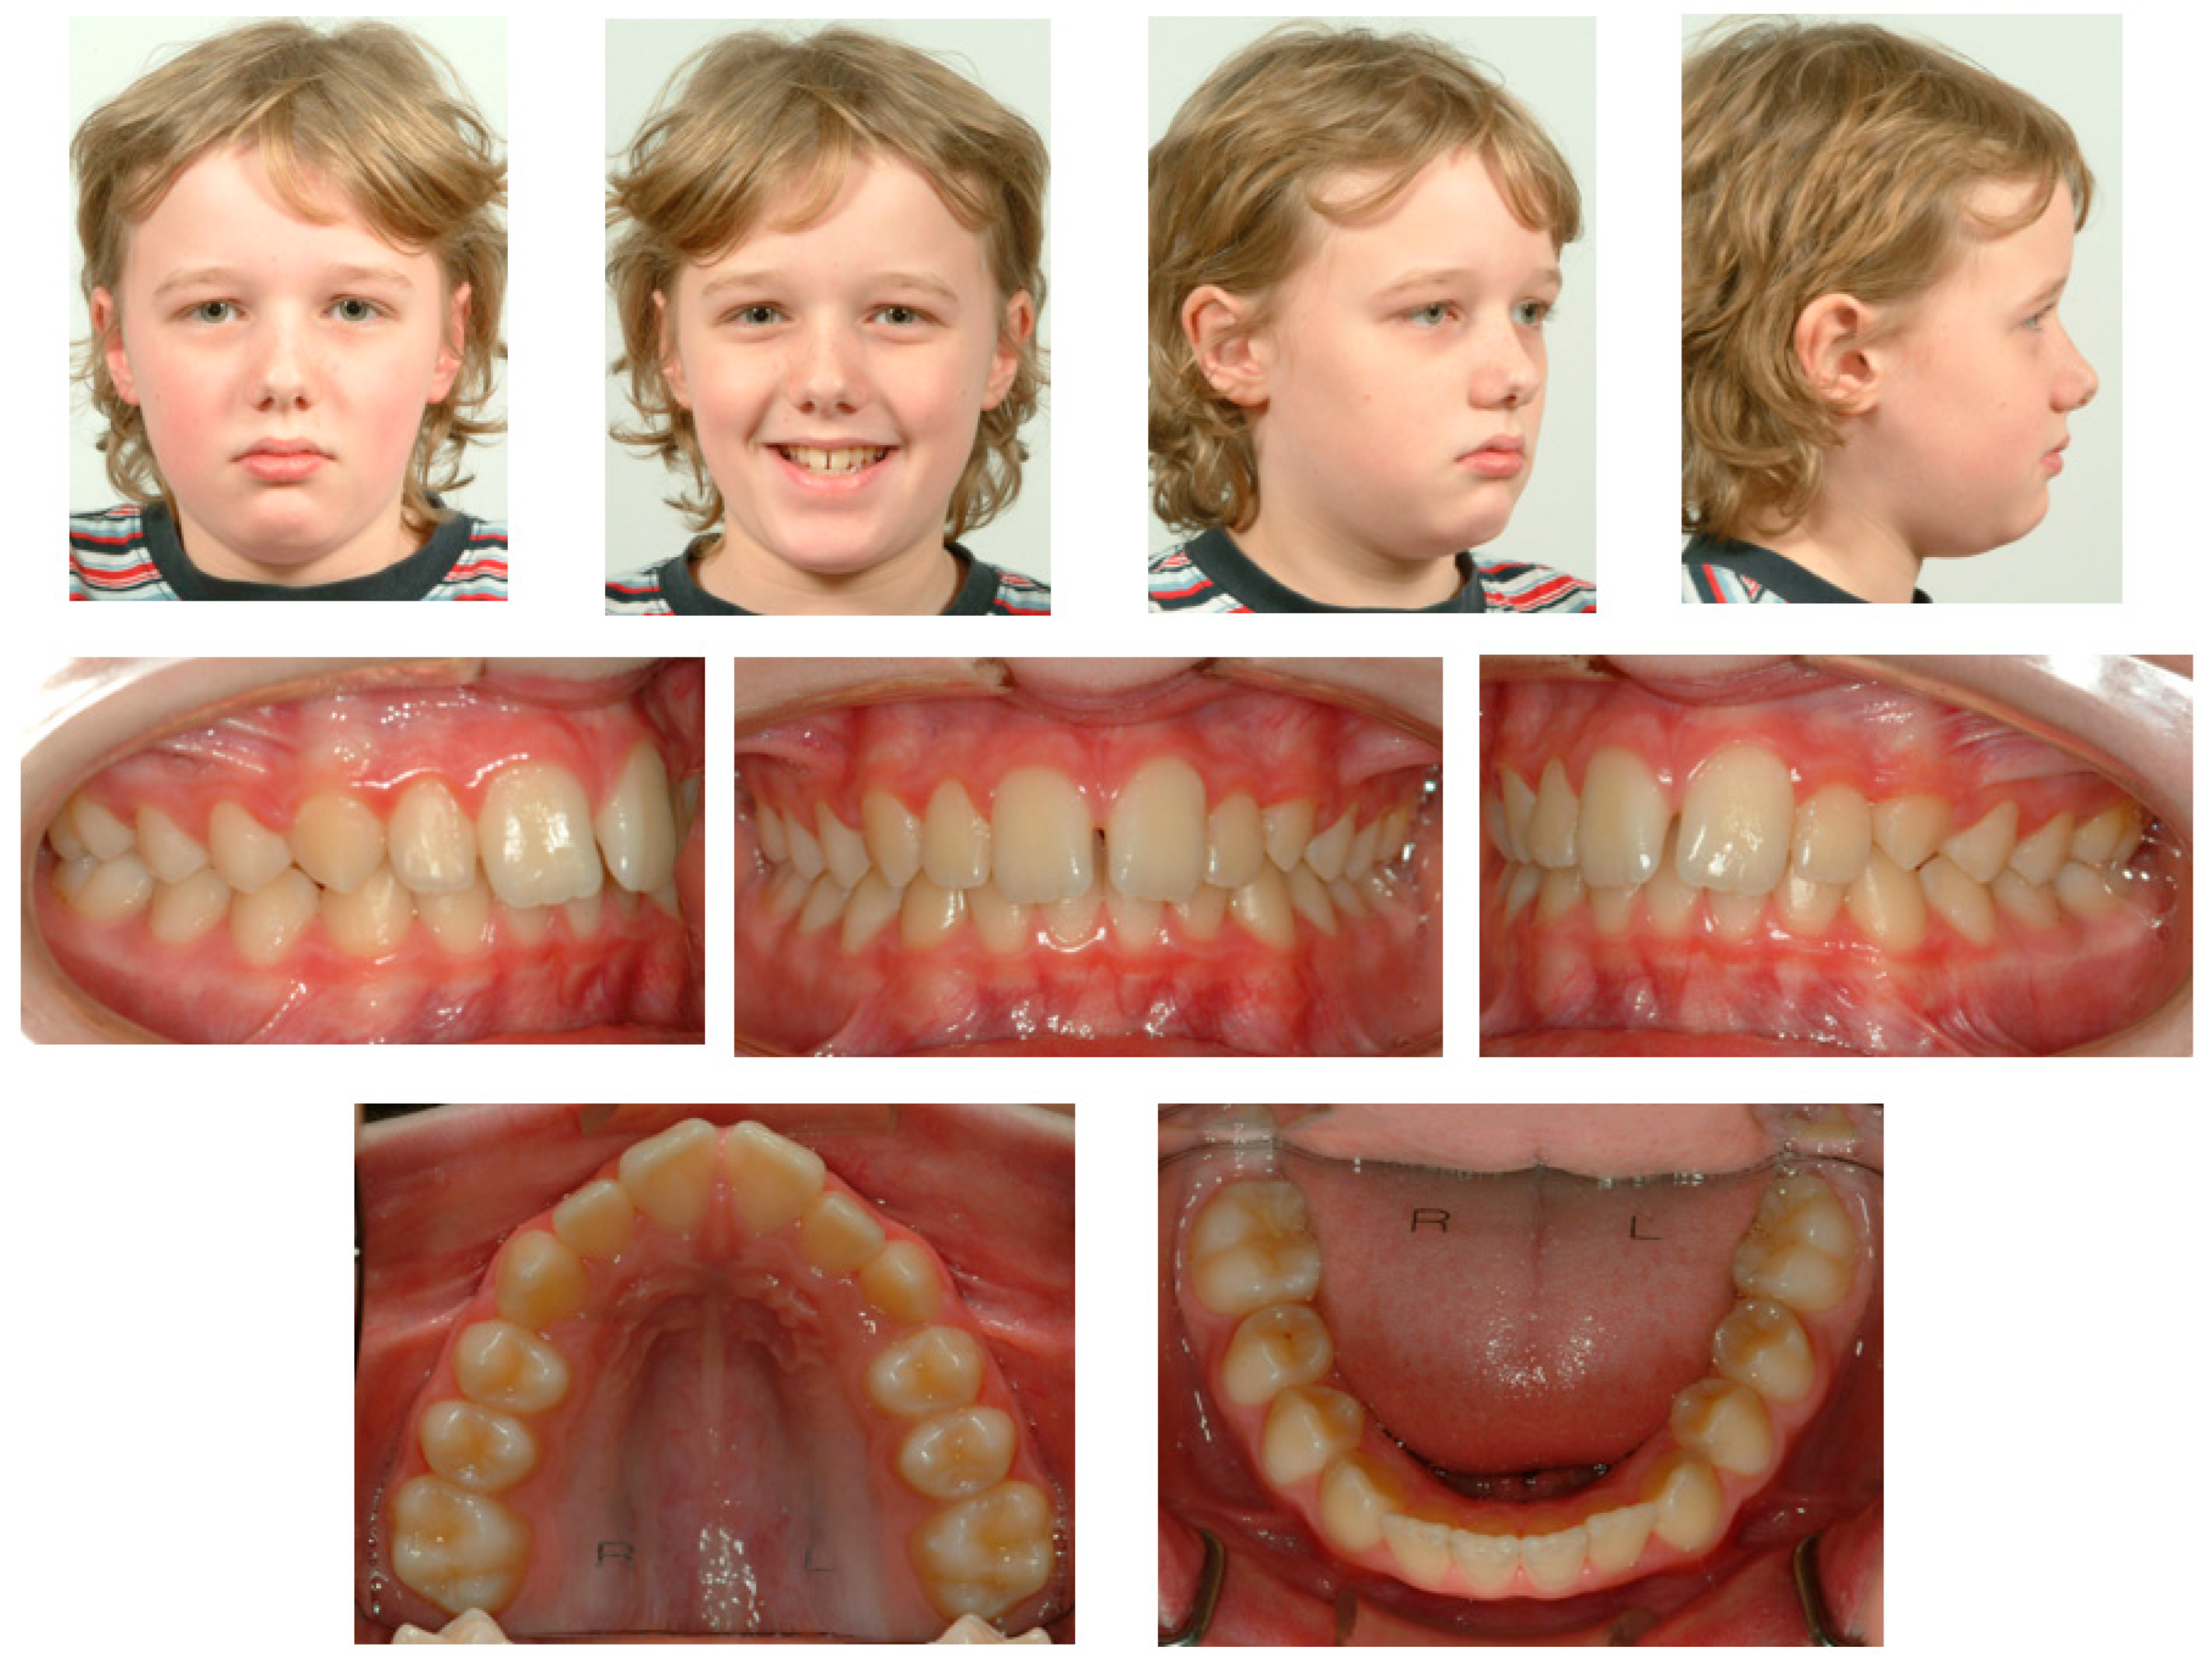

Currently, fixed retention is commonly used in orthodontic practice [7,8]. Previous research on the long-term outcomes showed that when using a flexible spiral wire (FSW) retainer bonded to the mandibular anterior segment, the alignment is stabilized in 90.5% (200/221) of cases after 5 years of retention [9]. However, these fixed retention appliances may also fail or have adverse effects. Recently, a systematic review was conducted to evaluate the available evidence on the failure of fixed retainers and reported that fixed retainers fail in a range of 7.3% to 50%, according to which detachment at the adhesive–enamel interface was the most commonly reported type of failure [10]. Other observed adverse effects of fixed retainers in the orthodontic literature are detachment at the adhesive–wire interface [11], wire fracture [12], wire untwisting [13], and calculus accumulation [14,15]. Wire untwisting may lead to unwanted changes in the tooth position and can be associated with the development of gingival recessions [13,16,17]. Other causes of unwanted tooth movements can be tongue thrust or personal habits [18,19]. A clinical case of unwanted tooth movements during the retention phase is presented in this case report. This case showed that the unwanted tooth movement was the direct result of an untwisting FSW, because the maxillary teeth were displaced in a different direction from the original tooth position (Figure 1), which clearly showed that this was not a case of simple relapse. The early recognition of these unwanted tooth movements is paramount for patients and clinicians to prevent the associated negative consequences [20].

Figure 1. Extra-oral and intra-oral photographs before first orthodontic treatment.